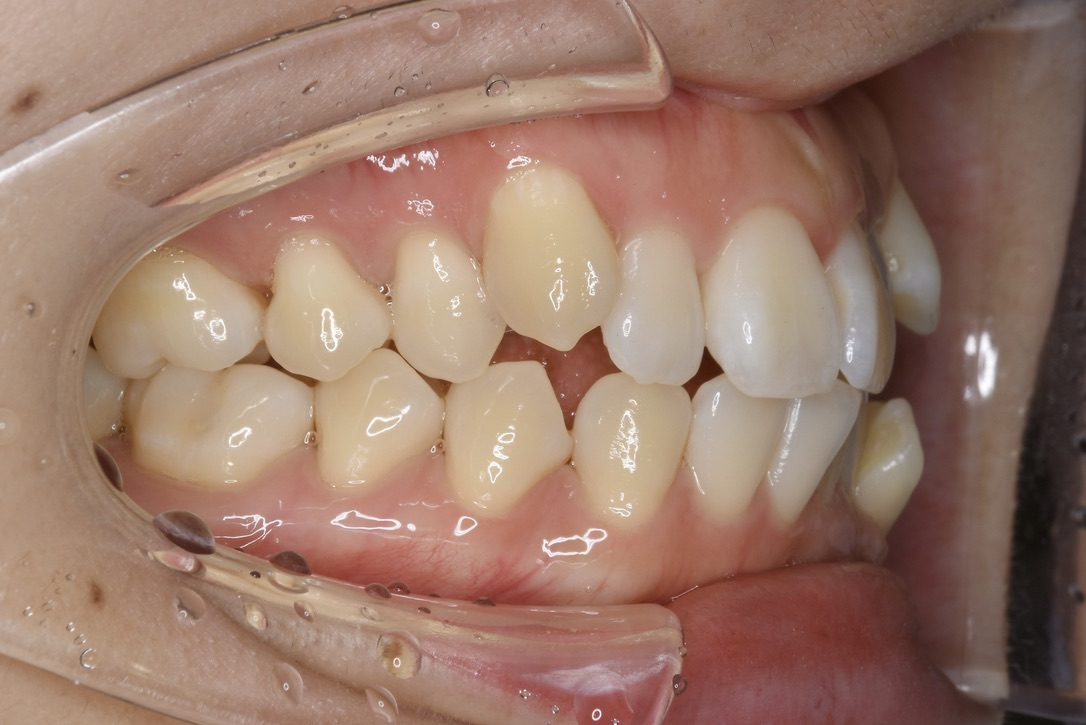

| 主訴 | 写真を見て歯並びが気になる。特に下の前歯はガタガタが強く治したい。 |

|---|---|

| 診断名・主な症状 | 叢生 |

| 年齢 | 19歳 |

| 治療内容 | 上下とも歯並びの幅を広げることでできたスペースを利用して、ガタガタを解消しました。 |

| 使用装置 | 表側矯正(ワイヤー) 矯正用ミニインプラント |

| 抜歯部位 | 抜歯なし |

| 治療期間 | 1年10ヶ月 |

| 通院回数 | 25回 |

| 費用 | 91万円程度(税別) 220 |

| リスク・副作用 | 痛み、歯肉退縮、歯根吸収、抜歯に伴う出血や腫れが生じることがあります。 |